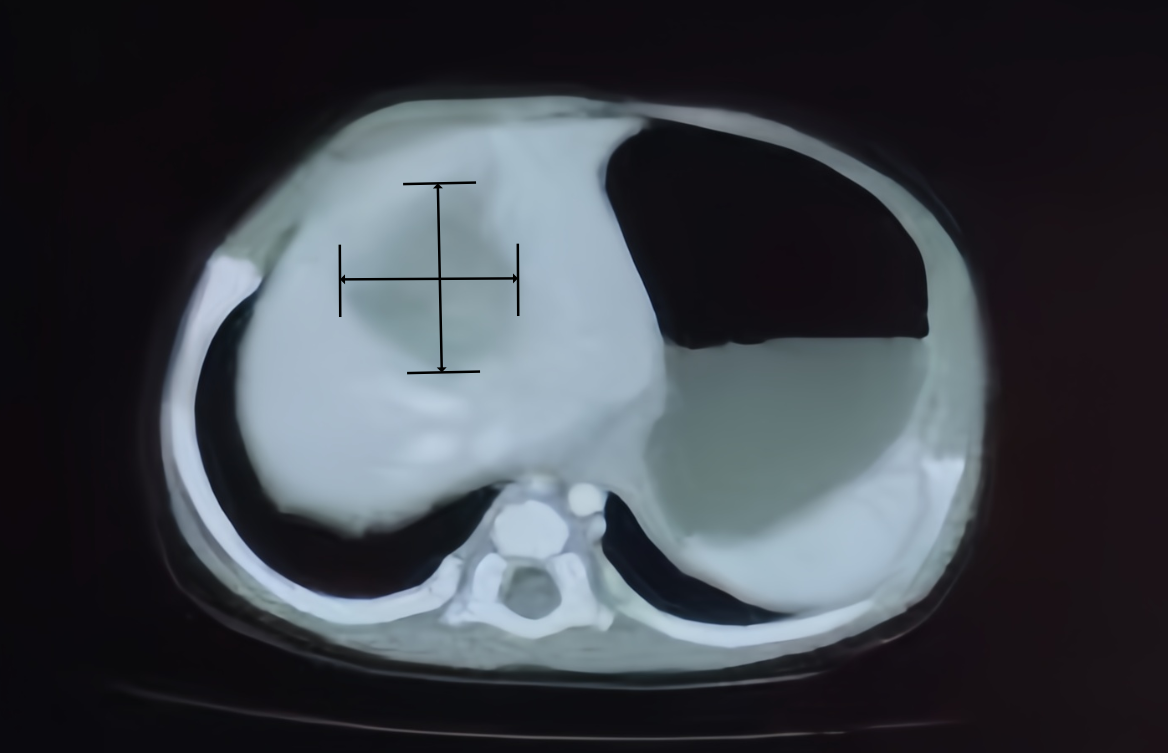

因为母亲妊娠高血压伴胎儿宫内窘迫,距离37周足月还有8周时间时,安安就提前来到了人世间,体重不到2斤。安安出生后在新生儿监护室接受严密的监护,也因此在45天常规查体时,发现了肝左叶肿瘤占位,6.8厘米*6.5厘米,肿瘤标志物之一的甲胎蛋白高达121000ng/ml,确诊为肝母细胞瘤。

“不放弃!”“有希望!”遇见李龙,百感交集的安安父母终于吃下了颗定心丸。李龙为安安制订了详细的诊疗方案,包括化疗、肝脏切除手术、术后综合治疗。经过第一阶段的治疗,安安体内的肝脏肿瘤明显缩小到4.4厘米乘以3.0厘米。而能否如期施行手术,除了儿外科医疗团队外,麻醉意见起着关键作用。与成人不同,婴幼儿肝切除手术,肿瘤相对体重比重大,血容量小,手术打击的耐受性低,稍有意外出血,就会导致休克而危及生命。所以国际上普遍认为,10斤以下婴儿肝切除是外科的高风险领域。早产的安安矫正月龄只有1个多月,体重刚达8斤,特别是安安的肿瘤位于肝脏的中心,比邻门静脉、肝静脉和下腔静脉大血管,极易出现静脉破裂大出血危险。很多医生看到安安的病情后,对于肿瘤切除手术危险望而却步,甚至建议放弃或者肝脏移植。“巨大的手术风险对麻醉操作、用药选择、体征监测、循环调整都提出了挑战。”麻醉科张欢说,安安是北京清华长庚医院迄今开展的早产低体重患儿行肝肿瘤切除的最小病例。